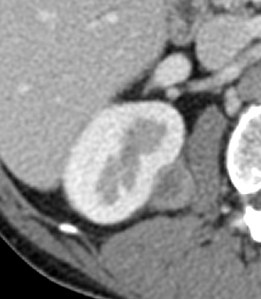

CASO 2: Paciente de 68 años con dolor en flanco izquierdo, fiebre y malestar general. A la exploración existe enrojecimiento de la piel con sensación de masa palpable y puño percusión muy positiva.

El paciente es alégrico al Iodo. Se realiza TC sin contraste para ampliar estudio.

Todos estos hallazgos están en relación con una Pielonefritis Xantunogranulomatosa que afecta al riñón derecho junto con una colección que ha fistulizado a región lumbar.

- Pielonefritis Xantunogranulomatosa.

- Es una forma infrecuente de pielonefritis crónica, de origen obstructivo, caracterizada por la formación de un absceso granulomatoso que puede extenderse al EPR-, severa destrucción renal y un cuadro clínico de fiebre, malestar general, dolor en el flanco y masa renal, a veces palpable.

- En placa simple podía verse un masa que renal con o sin borramiento de la línea del psoas. En ecografía, cálculos y aumento del tamaño renal en la forma difusa con múltiples áreas anecoicas correspondientes a las colecciones purulentas.

- Los hallazgos en TC pueden ser:

- Uni o bilateralidad de la lesión.

- Afección difusa o localizado.

- Litiasis de tipo coraliforme, calcificaciones intraparenquimatosas.

- Aumento difuso del tamaño renal.

- Áreas hipodensas o hipoecogénicas dentro de la lesión renal debidas a cálices dilatados, abscesos o áreas de necrosis parenquimatosa.

- Pobre o nula eliminación del medio de contraste en el riñón afectado.

- Compromiso inflamatorio que excede los límites del riñón y genera colecciones periféricas o extensión hacia vísceras vecinas.